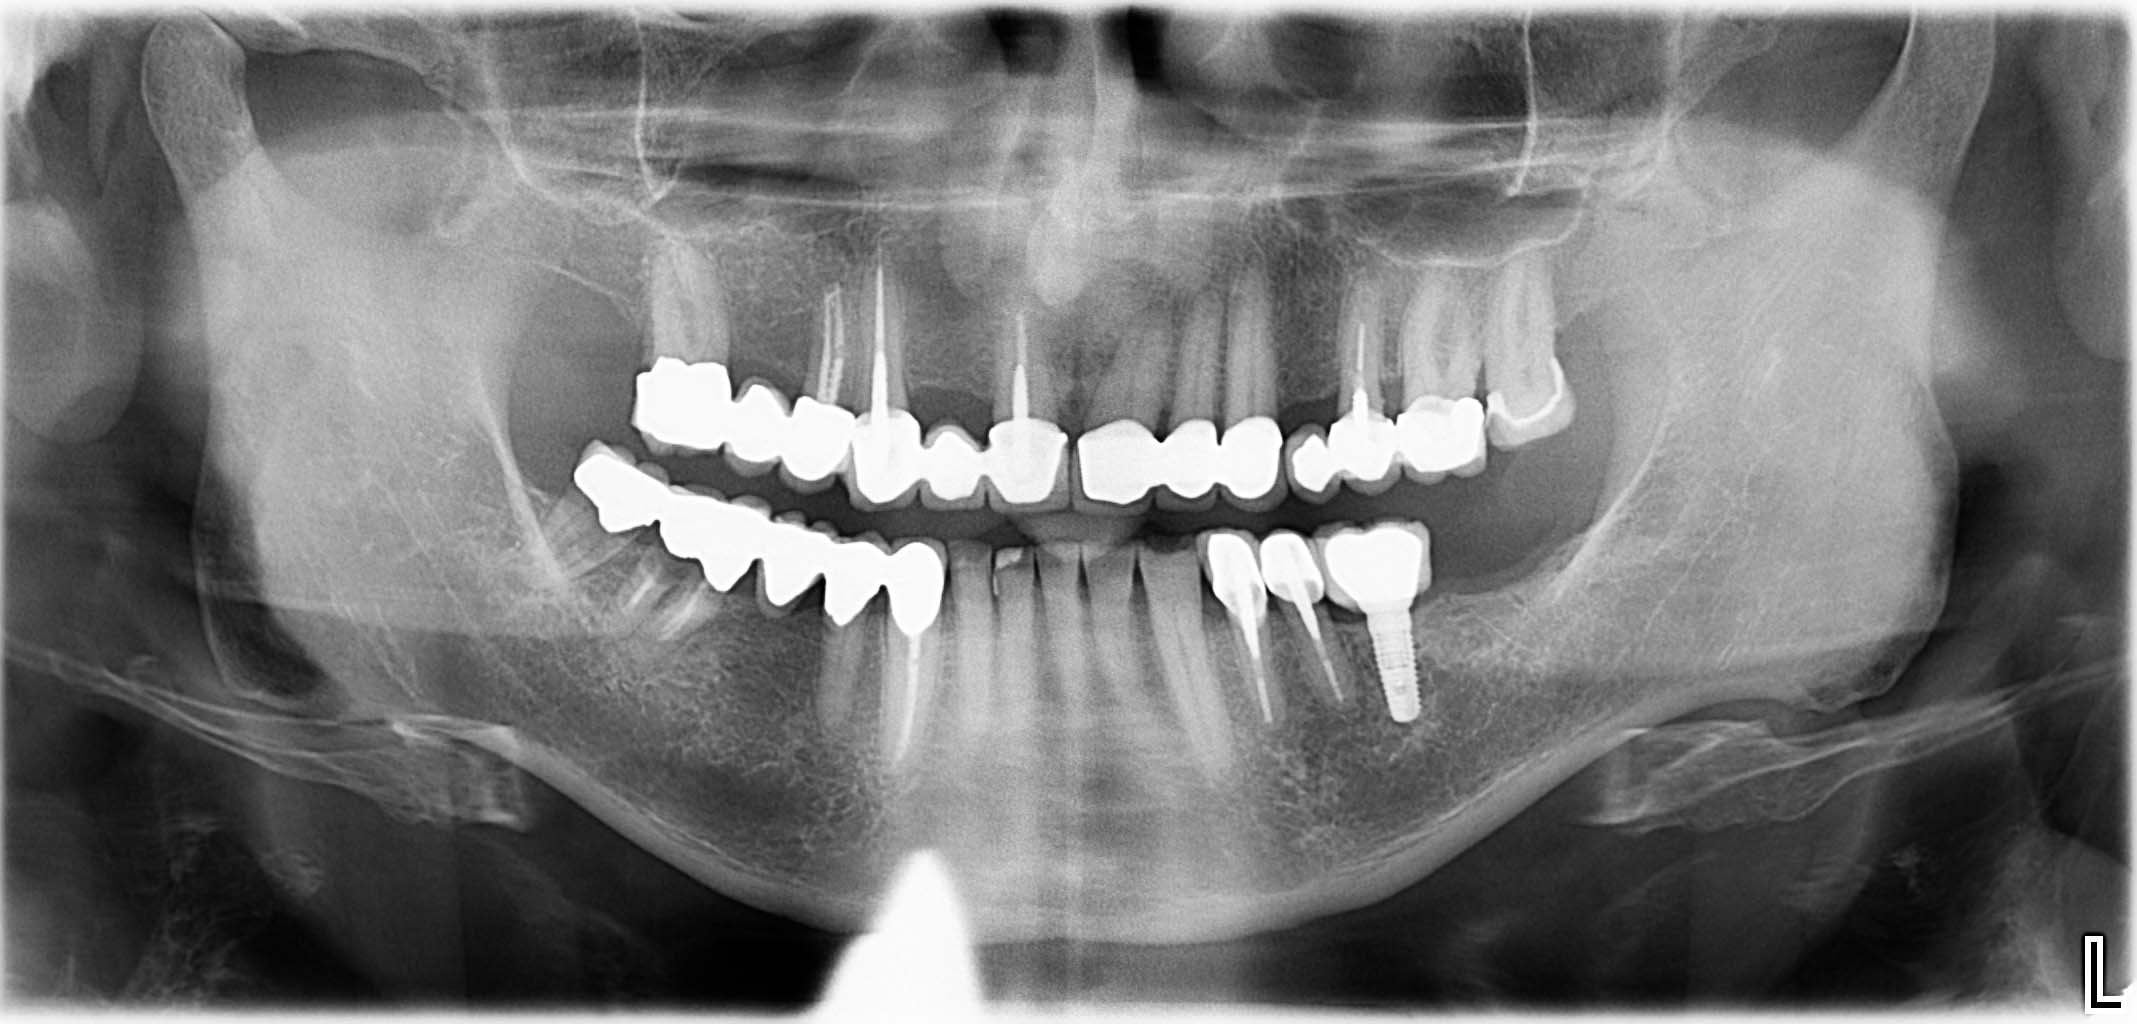

Erfolgreich implantierte Patientenfälle (klinische Fotos)